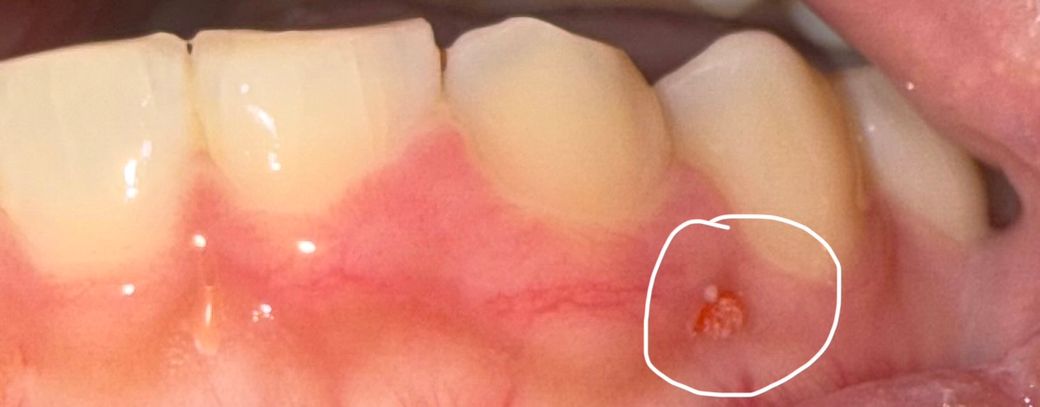

며칠 전까진 없었는데 오늘 양치하다가 발견했어요

이게 뭔가요? 왜 생긴 것이며 어떻게 해야

사라질지 궁금해요

후레쉬 터뜨려서 찍었습니다

단순 염증일수도 잇지만 치아 뿌리끝에 염증이 잇어서 그럴수도 있으니 치과에 가셔서 검진을 받아보시는게 좋을것같습니다.

며칠전까지 없다가 갑자기 생긴거라면 만성 염증은 아닐거고 세균이나 바이러스 감염으로 인한 구강병소로 의심됩니다